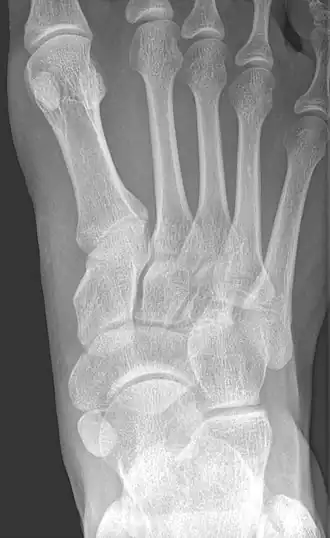

Os naviculaire cornéen